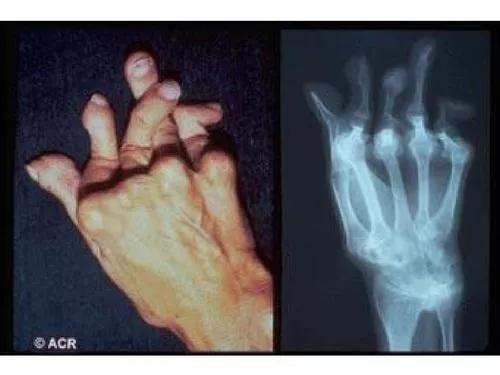

类风湿关节炎

这类关节炎病因不明确,症状表现与风湿性关节炎相似,发病也呈对称性、侵袭性,多关节发病,可以波及其他器官。

区别在于类风湿关节炎严重时会导致关节畸形和功能丧失,风湿性关节炎则不会。

随着病情发展,出现关节畸形、活动受限。心脏、肾脏、神经系统、消化系统等也会出现不同程度的症状。